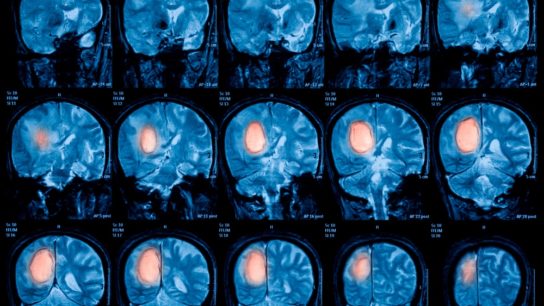

Researchers sought to develop and validate an MRI radiomics prediction model through a machine learning-based method to predict the survival of patients with glioma.